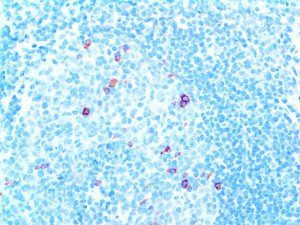

It is the ICU physician who is most likely to witness one of the deadliest manifestations of the abnormal immunological response, the cytokine storm syndrome (CSS). This response is also referred to by some as the cytokine release syndrome (CRS). CSS is characterized by continuous activation and expansion of macrophage and lymphocyte populations, which secrete large amounts of cytokines, causing the cytokine storm. This massive cytokine release is akin to hemophagocytic lymphohistiocytosis (HLH) disease, a syndrome characterized by initial unchecked and persistent activation of cytotoxic T lymphocytes and NK cells.

Clinical and laboratory manifestations of HLH include fever, enlarged liver and/or spleen, neurologic dysfunction, coagulopathy, liver dysfunction, cytopenias (i.e., low levels of erythrocytes, leukocytes, and/or platelets), hypertriglyceridemia, hyperferritinemia, hemophagocytosis, and eventually diminished NK cell activity as the immune system becomes progressively paralyzed. HLH can be familial (primary HLH) or secondary to another disease process (sHLH), such as rheumatic disease, in which it is referred to as macrophage activation syndrome (MAS, characterized by elevated ferritin).